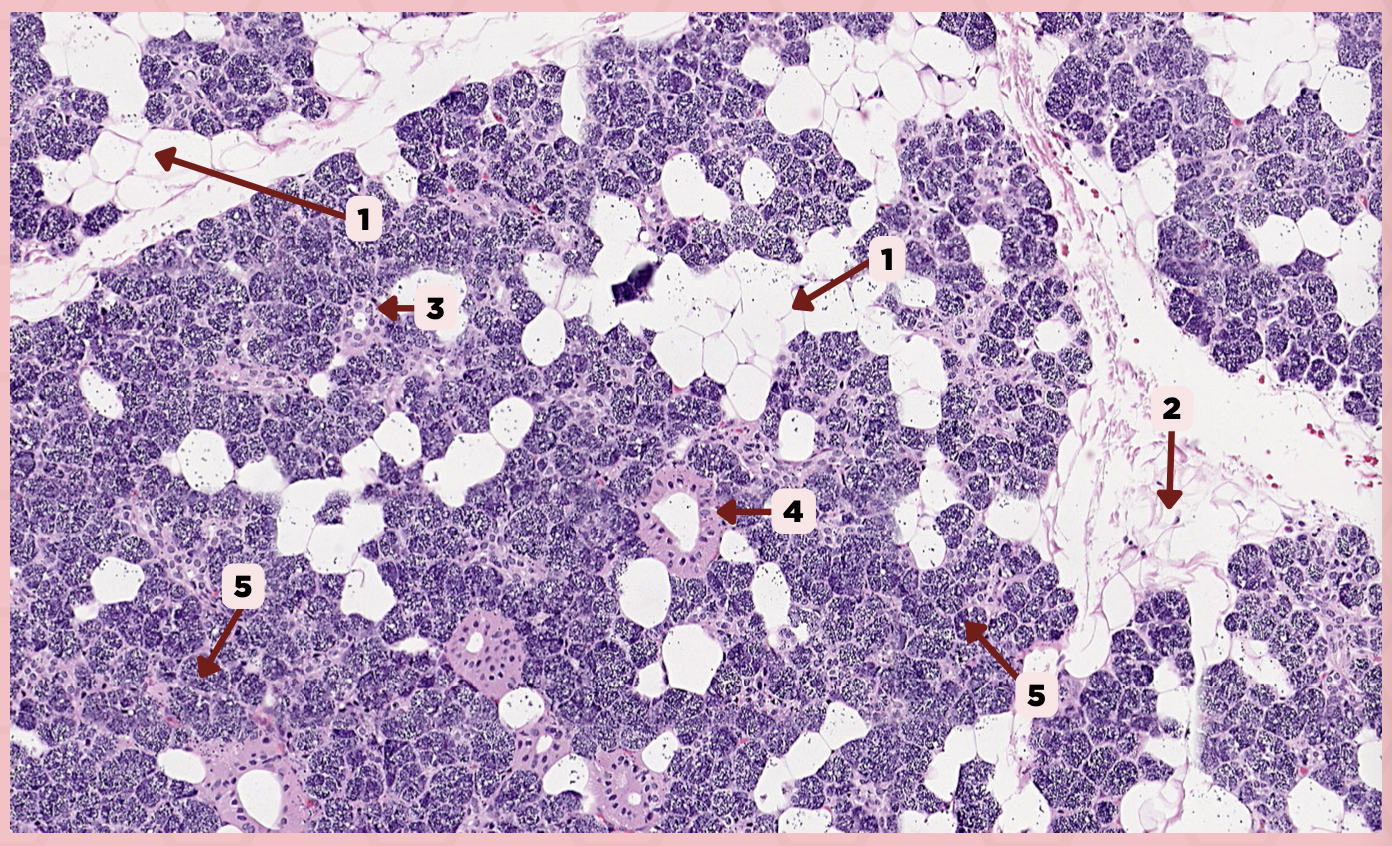

Parotid

Identify the specimen.

Capsule

Identify the structure labeled as 1.

Septa

Identify the structure labeled as 2.

Lobule

Identify the structure labeled as 3.

Lymph Node

Identify the structure labeled as 4.

C) Septa

Which of the following structures shown delineate the lobes and lobules of the parotid gland?

A) Capsule

B) Lobule

C) Septa

D) Lymph Nodes

A) Capsule

Which of the following structures encapsulates the parotid gland?

A) Capsule

B) Lobule

C) Septa

D) Lymph Nodes